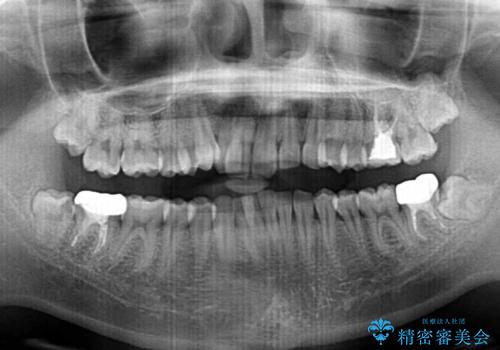

- 上顎の重なっている前歯を気にして来院された患者様です。

八重歯改善には抜歯が必要で、八重歯の移動量が多く、更には右側にずれている正中を改善する必要がありました。

インビザライン単体での治療は困難と判断し、補助装置により八重歯移動後にインビザラインを用いることとしました。